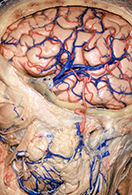

<手術方法>

左前頭側頭開頭で動脈瘤クリッピング術を行った。

手術中は脳血管撮影装置を用いたHybrid手術を施行し、動脈瘤の消失を手術中に確認する。

手術中MEP(運動神経)VEP(視力)モニタリングで術後の視力低下や手足の麻痺を予防する。